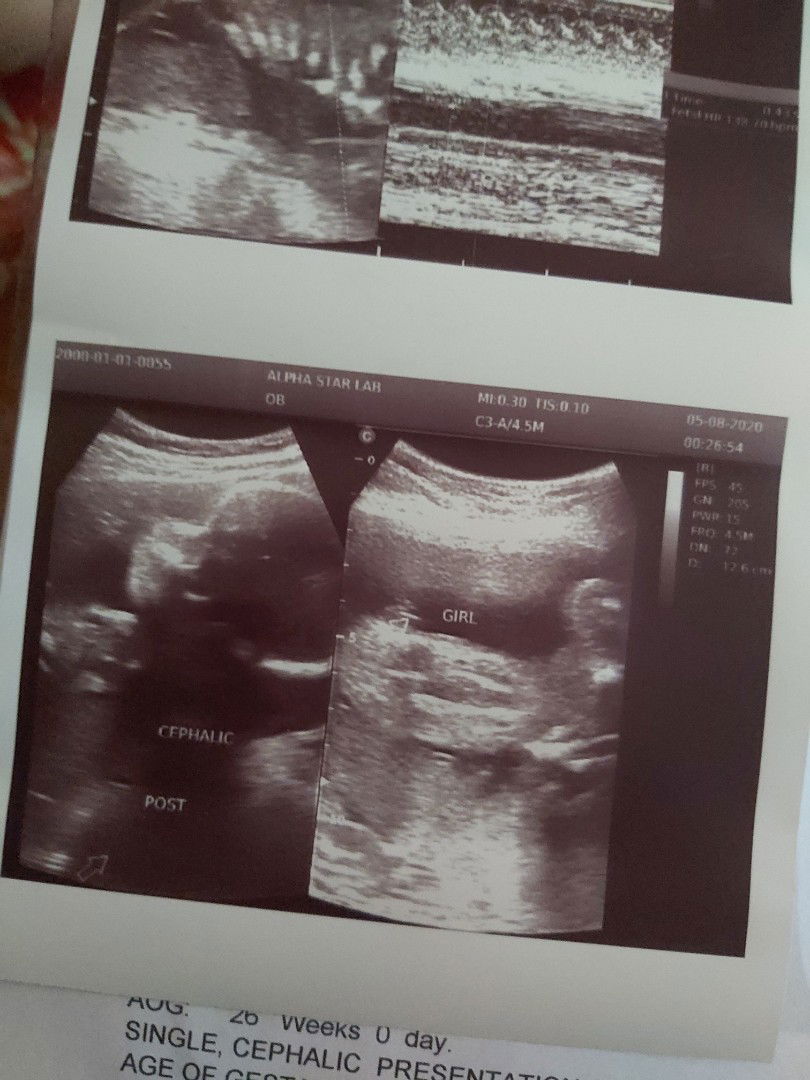

#TeamAugust

Hi mommies!! Advance happy mother's day to all momshies out there and para sa mga first time mom like me,super sarap pala sa feeling na mag celebrate nito ? Finally,nakapag-pa ultrasound na din and kampante na kasi okay si baby ?? We're having a baby girl!! ?? Weighing 928 grams,cephalic position and posterior ? 26 weeks today!! Can't wait to hold and kiss my lo!! ??